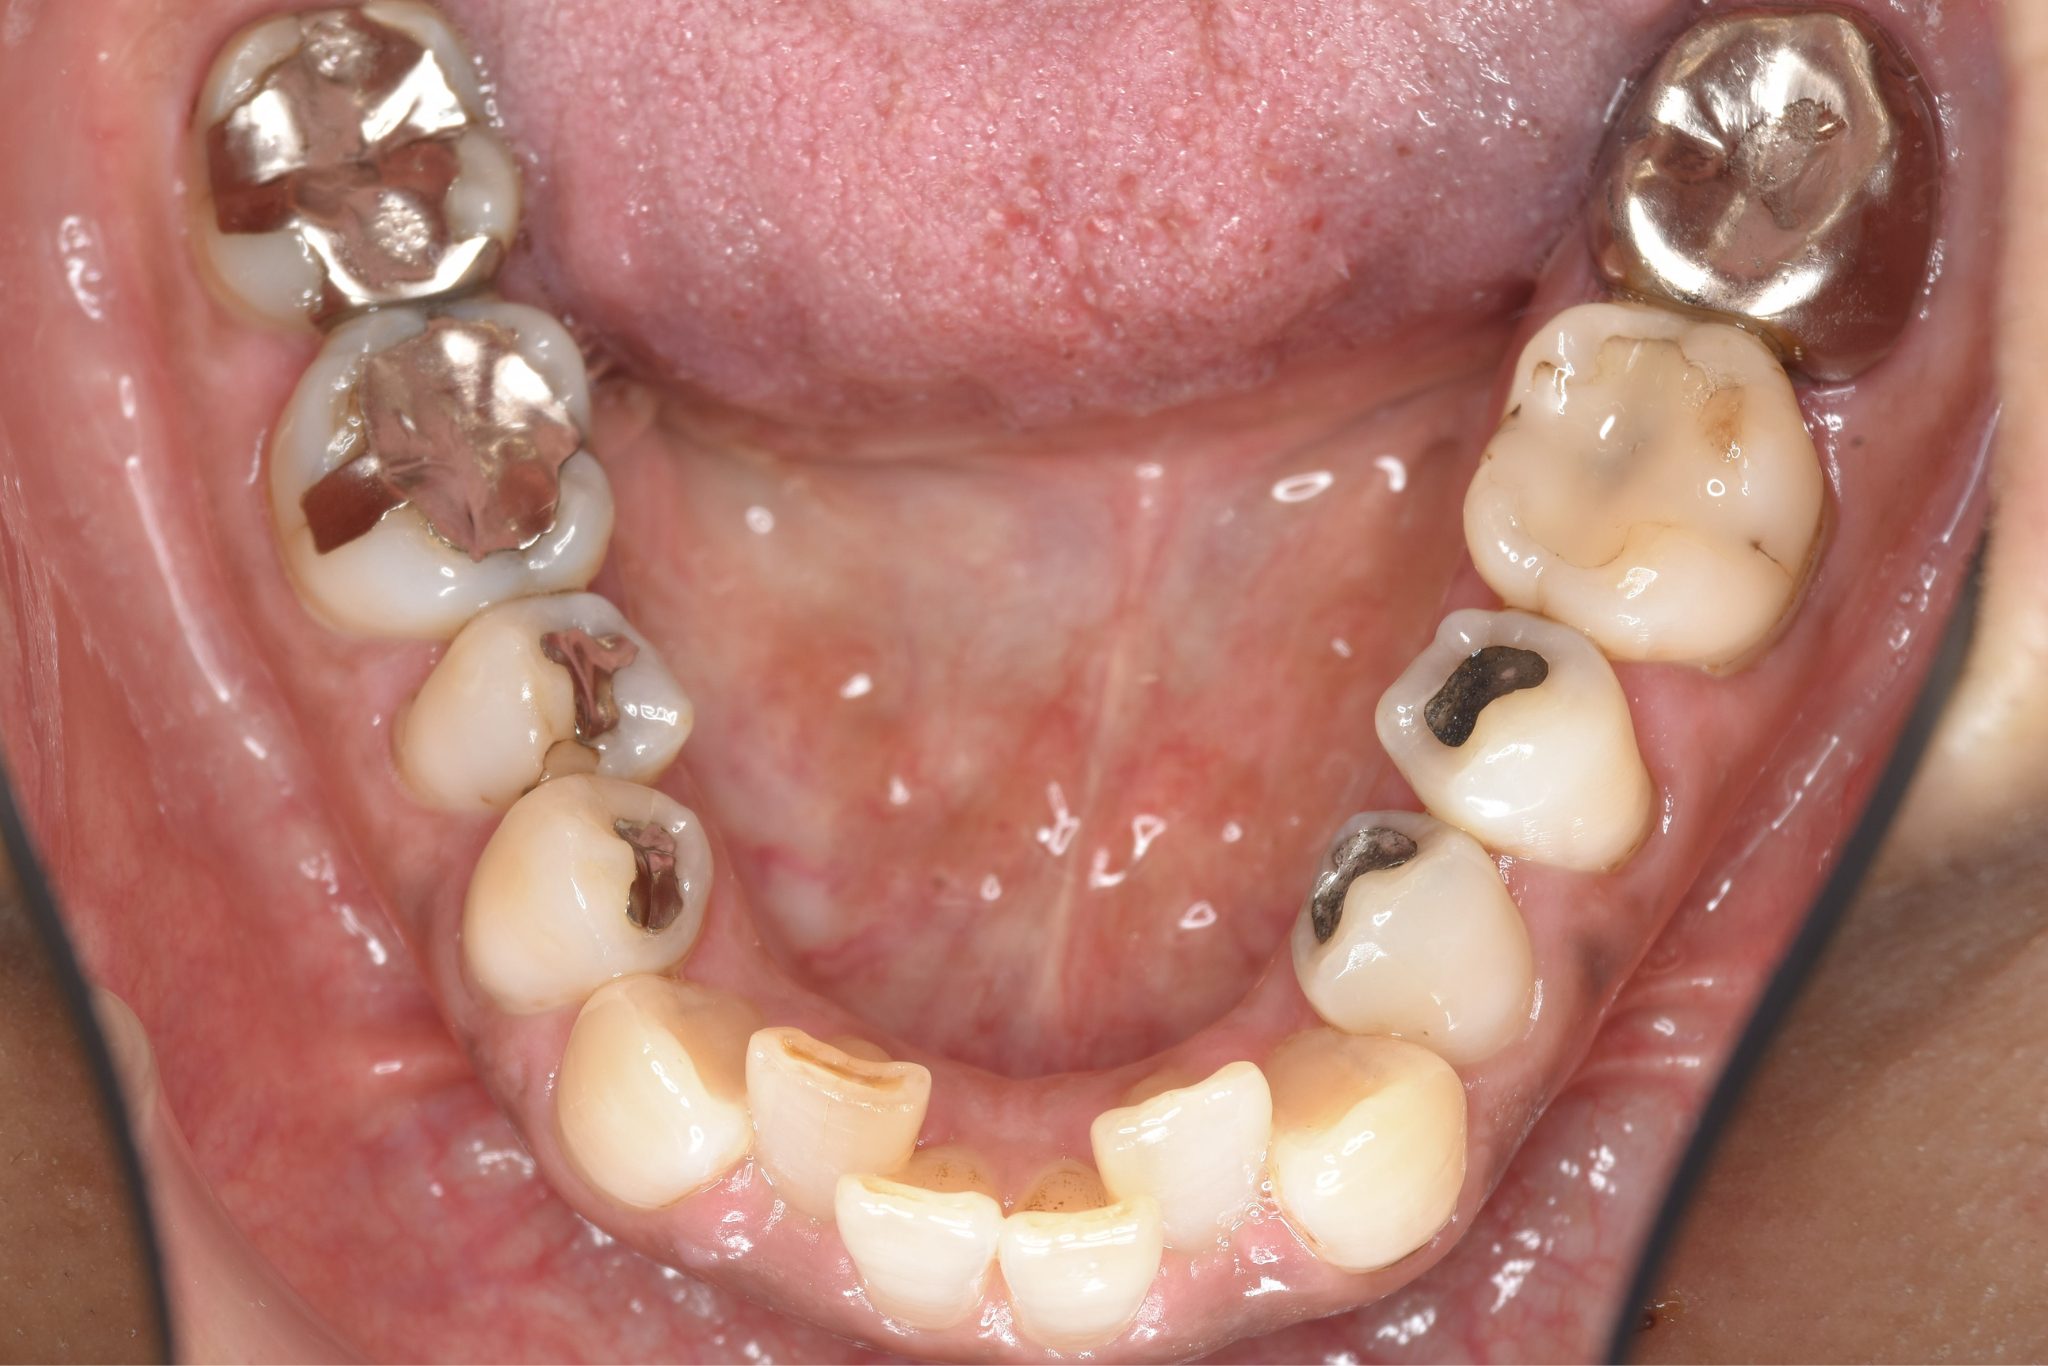

ビフォー

ワイヤー矯正治療|症例_588

主訴 かみ合わせ ※抜歯あり

施術内容 MSEと下顎リンガルアーチを用いて上下顎骨を拡大した。

その後下顎前歯を1本抜歯してマルチブラケット装置を用いて

歯牙を配列し良好な咬合を獲得した。側貌は改善した。